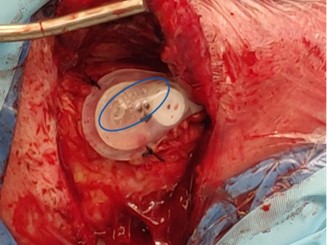

It is known in clinical practice that small air bubbles often remain in the valve reservoir at the time of placement, and this residual air can be difficult to purge (Figure 1). While the clinical relevance of air bubbles is unclear, one case report suggests that they could be a root cause of VP dysfunction [5]. This type of failure would be radiologically occult, as air is not visible in radiopaque catheters and would therefore currently go undiagnosed.